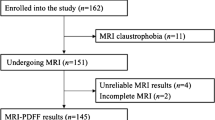

Patients were enrolled between January 2021 and May 2022 at the Department of Pediatrics, Sapienza University of Rome, Italy. The main inclusion criteria were age <18 years and a body mass index (BMI)-for-age>85th percentile (World Health Organization [WHO] growth charts, 5–19 years [14]). The exclusion criteria were the presence of diabetes mellitus (type 1 or 2), thyroid illnesses and liver diseases other than NAFLD. The parents or legal guardians of all patients signed an informed consent form before enrollment. Calibrated scale and stadiometer were used for body weight and height assessment, respectively; waist circumference was taken with an inextensible tape at a point midway between the inferior margin of the lowest rib and the iliac crest [15]. Obesity prevalence was assessed using both the WHO [16] and International Obesity Task Force (IOTF) [17] definitions.

Out of the 36 children and adolescents recruited in the study (17 females), MRI showed a PDFF value ≥5.6% in 22 patients (males: n=13 [59%]). Obesity prevalence ranged from 66.6% (n=24) to 44.4% (n=16), whereas overweight affected 33.3% (n=12) to 55.5% (n=20) of the sample (IOTF and WHO definitions, respectively). The general characteristics of the study sample, categorized according to hepatic steatosis status, are expressed as medians (1st–3rd quartile) in Table 1.